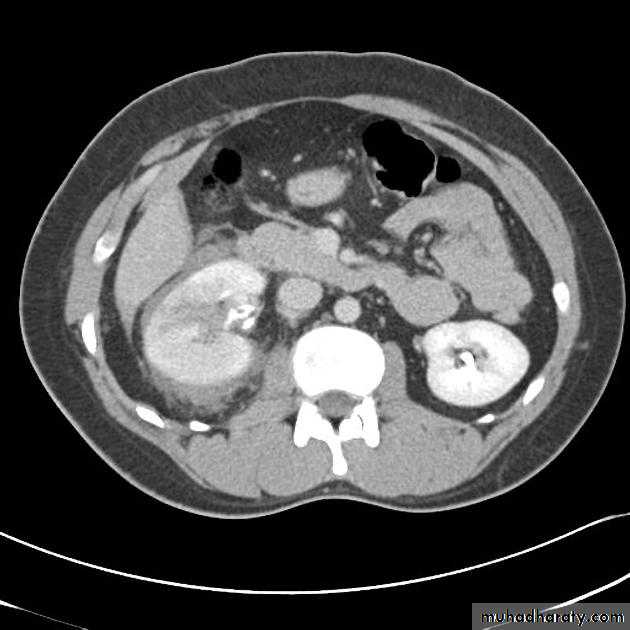

RENAL CELL CARCINOMA(RCC)

Most common malignant renal masses.Spherical or lobulated similar density to the adjacent renal cortex.

May have areas of necrosis.

Enhances heterogeneously and less than that of the adjacent renal parenchyma.

CT is sufficiently accurate so that preoperative biopsy is rarely performed.

Staging is best by CT except for vascular invasion where MRI will be superior.

Staging parameters include : local direct spread, retroperitoneal L.Ns enlargement, liver adrenal or pancreatic metastasis and renal vein or IVC involvement.